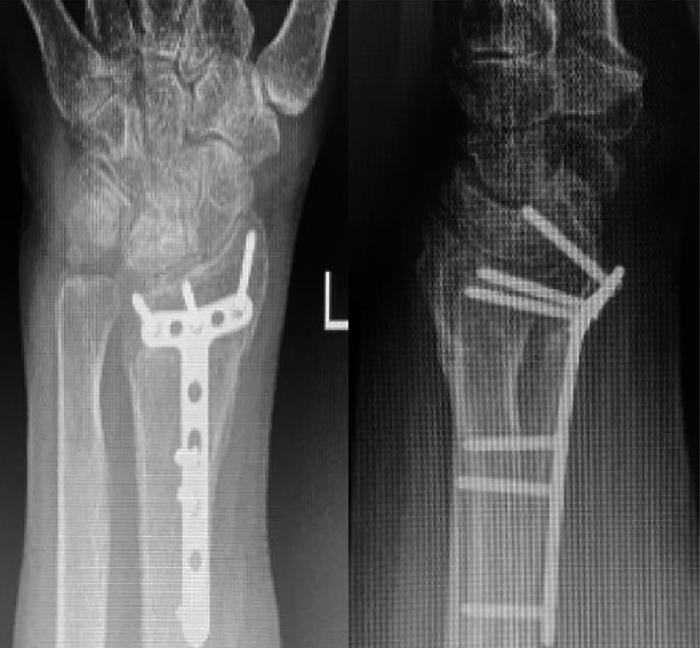

次年3月4日当地人民医院X线片(图2)示:左桡骨远端、尺骨茎突骨折复查,桡骨内固定中,断端对位对线好,尺骨茎突骨折断端对位对线可,局部可见骨痂形成,腕关节间隙变窄,周围软组织略肿胀。

图2